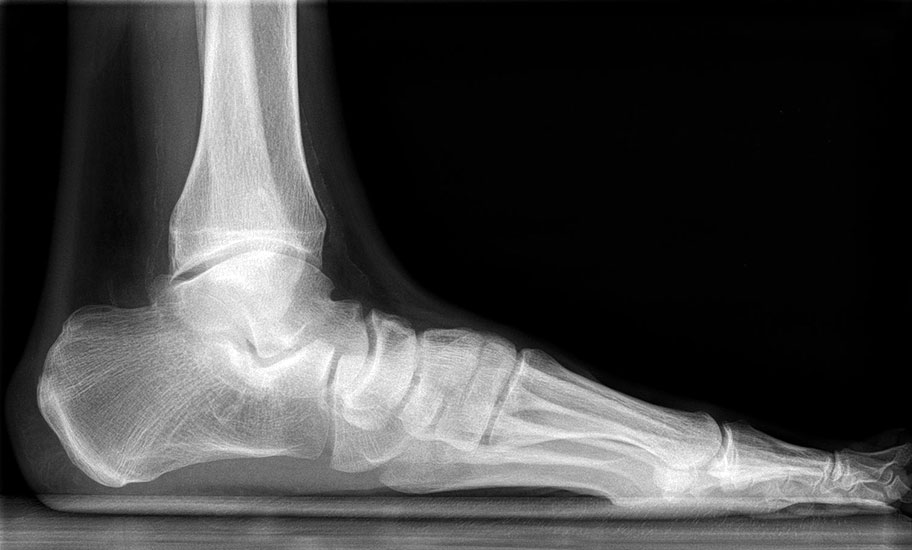

Auf dem linken Bild (a) Varusarthrose des oberen Sprunggelenks mit deutlicher Mehrbelastung der medialen Gelenkanteile. Dort bereits deutlich sichtbarer Knorpelverlust. Rechtes Bild (b) Valgusarthrose des oberen Sprunggelenks. Erhöhte Druckbelastung in de

Abbildung 1